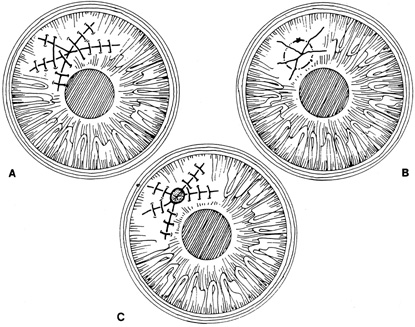

Placement of sutures through the visual axis should be avoided. If it is necessary to pass sutures near the visual axis, they may be placed on each side of, but not directly through, the axis itself. In addition, the bite closest to the visual axis may be made shorter, thus avoiding this area (Fig. 6). A “no-touch” technique also may be used to minimize trauma at the visual axis. With this technique, the eye is secured by grasping the globe with forceps away from the cornea. The suture needle end is then placed perpendicular to the corneal surface, and the needle is rotated through the corneal tissue following the needle's curvature (Fig. 7).8